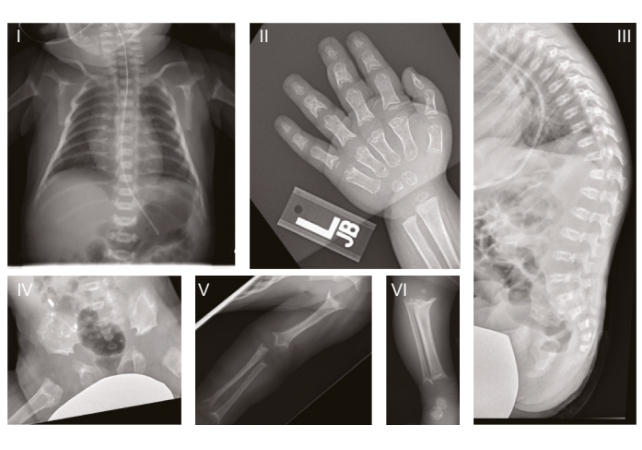

In humans, this specific ultra-rare genetic disorder is called Sedaghatian-type spondylometaphyseal dysplasia (SSMD), which is characterized by severe brain and skeletal abnormalities. It was first described in 1980, and since then, only a few dozen cases have been officially recorded, many describing children dying in early infancy.

The study focused on three children with SSMD in the US who showed varying degrees of brain atrophy and who had mutations in the same functional region of the GPX4 gene. These results were then used for further study in mice and in lab-grown brain cells, created from the skin cells of an SSMD patient.